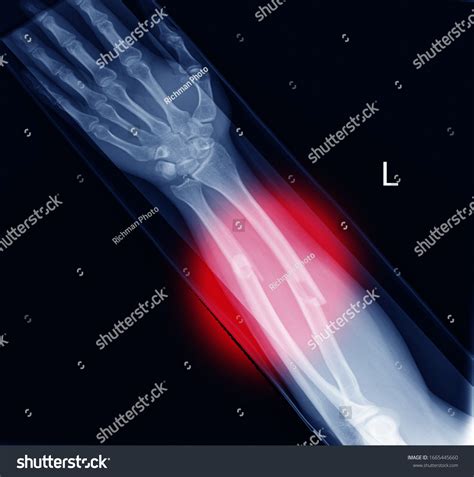

Diagnosing a Fractured Radius Ulna

Diagnosing a fractured radius ulna involves a combination of physical examination and imaging tests. The diagnostic process typically includes:

• Physical Examination: A healthcare provider will examine the injured area, checking for tenderness, swelling, and deformity.

• X-Rays: X-rays are the primary imaging tool used to confirm the presence and severity of a fracture. They provide detailed images of the bones and can show the exact location and type of fracture.

• CT Scans or MRI: In some cases, a CT scan or MRI may be ordered to provide more detailed images, especially if the fracture is complex or if there is concern about soft tissue damage.